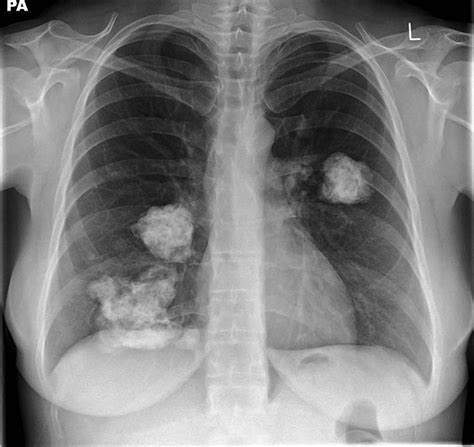

• Chest X-ray: A chest X-ray can reveal the presence of calcium deposits in the lungs.

• CT Scan: A computed tomography (CT) scan provides detailed images of the lungs and can help identify the location and extent of the calcification.

Calcification in lungs refers to the abnormal deposition of calcium salts in the lung tissue. This process can affect the lungs' structure and function, leading to various respiratory issues. The calcium deposits can form in different parts of the lung, including the alveoli, bronchi, and blood vessels. The severity and impact of calcification in lungs can vary widely depending on the underlying cause and the extent of the deposits.